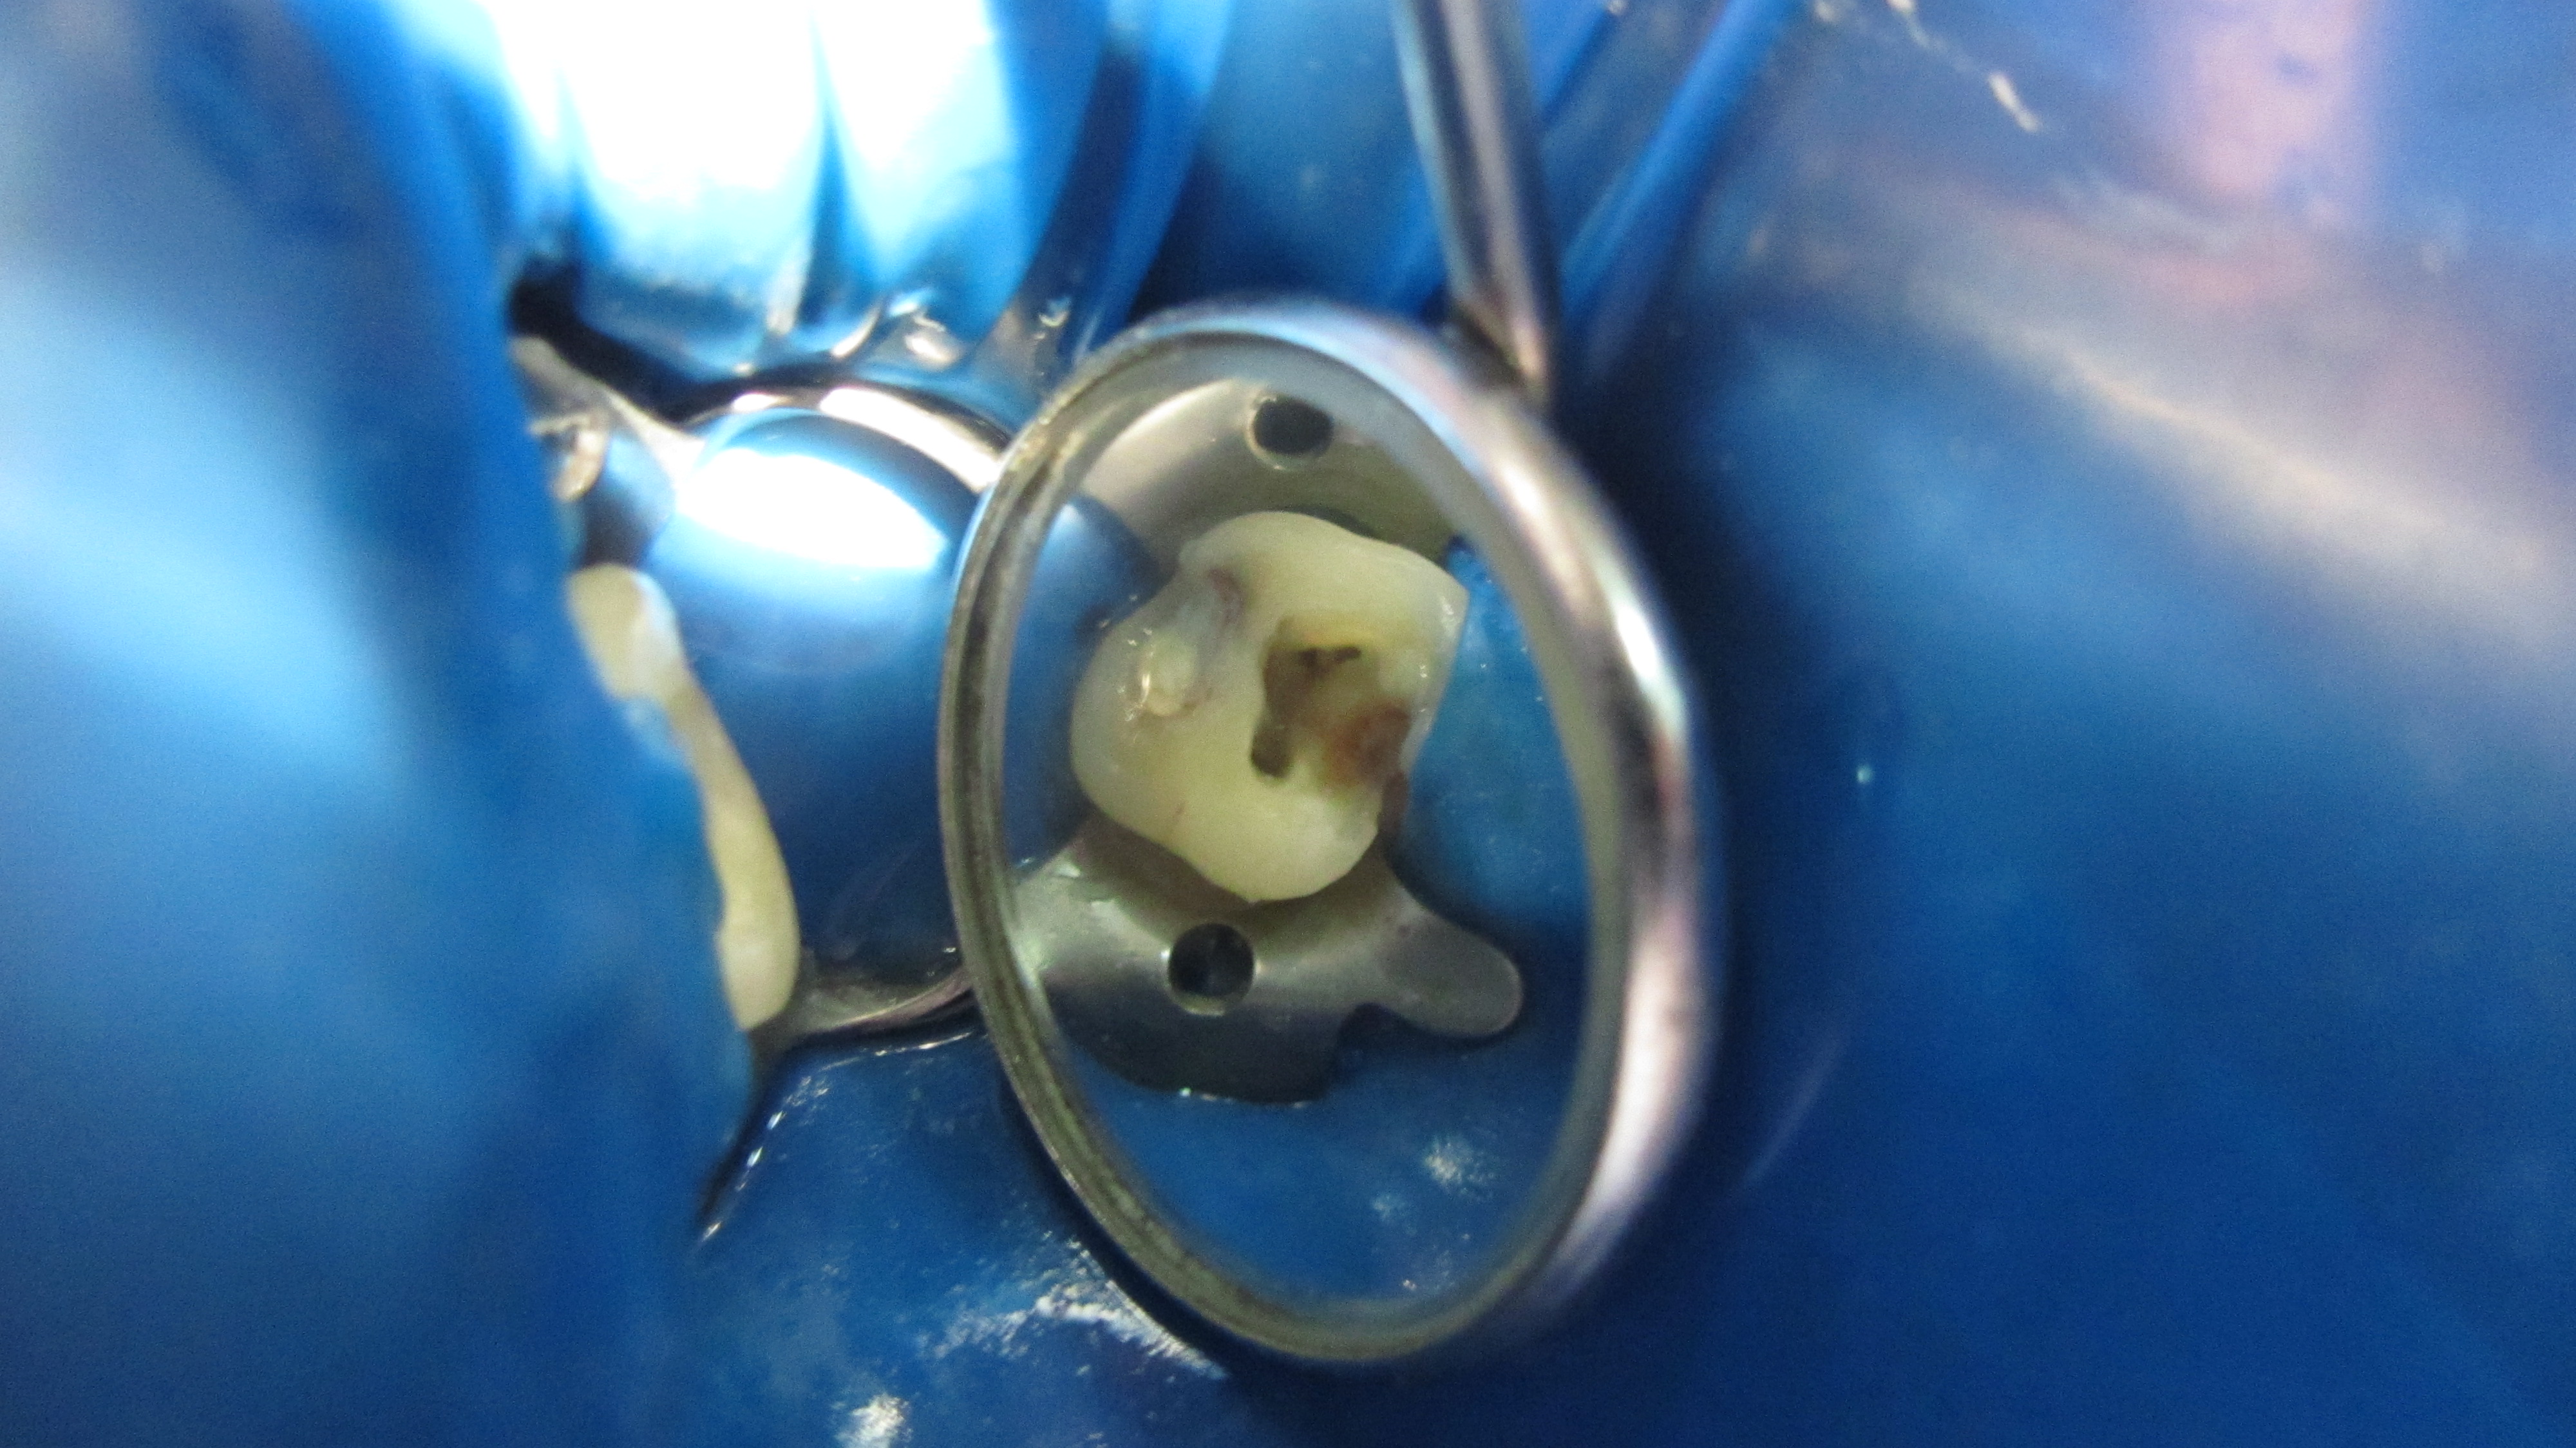

Dental Dam Isolation